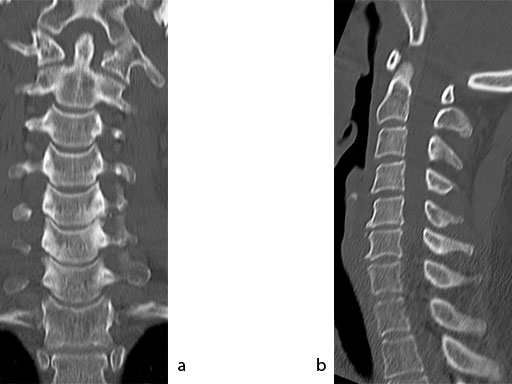

A 51-year-old woman was affected by cervical radiculo-myelopathy due to spinal and neuroforaminal stenosis. The preoperative CT scans are shown at Fig 4 and MRI at Fig 5.